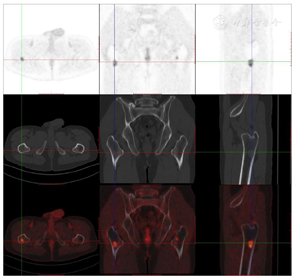

头颅顶可见术后瘢痕,愈合可,后颈可见一长约10 cm术后愈合瘢痕。头颅压痛、包块。发病来,患者神志清,精神可,睡眠可,饮食及大小便正常,体重无明显变化。2021年10月8日行PET-CT示左侧额顶部颅骨术后改变;左侧颞极片状高密度影并邻近骨质破坏,代谢增高(图A);左前纵膈肿块,代谢增高(图B);双肺散在结节,代谢轻度增高(图C);右侧锁骨、左侧第6肋,胸9-腰1、3椎体及其附件骨、双侧髂骨及双侧股骨近端多发混合型骨质破坏,代谢不同程度增高,考虑多发转移瘤(图D,图E,图F);2021年10月10日复查CT示右肺下叶可见结节影,直径约1.5 cm,增强扫描轻度强化;前上纵膈可见类圆形软组织密度影,边界清楚,大小约4.4 cm×3.3 cm,增强扫描轻度强化。于2021年10月11日在局部浸润麻醉下行CT引导下经皮纵膈占位穿刺活检术。病理结果示:肺穿刺组织内见恶性肿瘤,符合转移性间变性脑膜瘤。2021年10月13日MRI示:多发胸椎椎体及附件、所扫及L1椎体异常信号,结合病史,考虑为转移瘤可能。